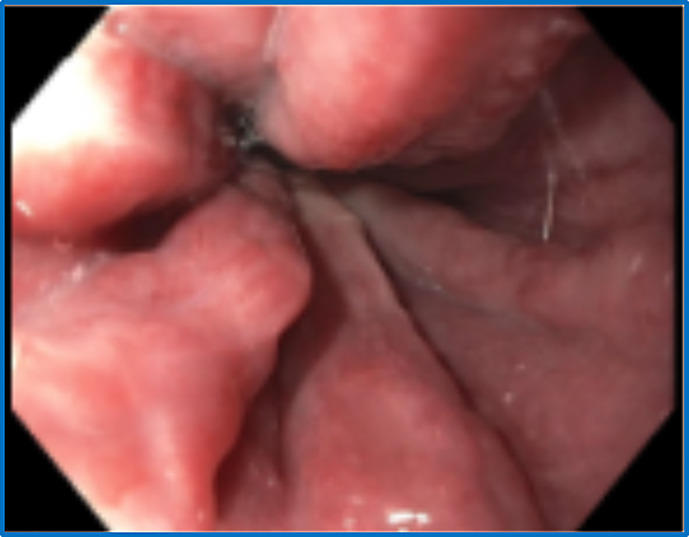

简介特纳综合征较少累及胃肠道系统。据报道,特纳综合征患者的肝脏病变是由非酒精性脂肪变性和脂肪性肝炎引起的,病毒性肝炎和酒精性肝炎则较为少见。门静脉高压通常与肝硬化有关,但也有一小部分患者在没有肝硬化的情况下也会出现门静脉高压。门静脉高压症在特纳综合征患者中非常罕见,在特纳综合征患者无肝硬化的情况下更少见:在此,我们报告了一例经肝活检证实的非肝硬化性门静脉高压症,其病因是门静脉血管病变:结论:临床高度怀疑可导致特纳综合征患者门静脉高压症的早期诊断和治疗,从而减轻门静脉高压症并发症的负担。

Case presentation: Herein, we report a case of liver biopsy-proven non-cirrhotic portal hypertension due to portosinusoidal vascular disease.